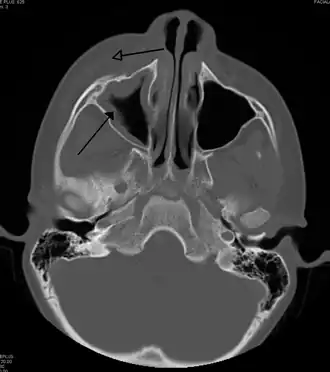

For sinusitis lasting more than 12 weeks, a CT scan is recommended.[66] On a CT scan, acute sinus secretions have a radiodensity of 10 to 25 Hounsfield units (HU). In a more chronic state, they become more viscous, with a radiodensity of 30 to 60 HU.[69]

-

Maxillary sinusitis caused by a dental infection associated with periorbital cellulitis -

Frontal sinusitis -